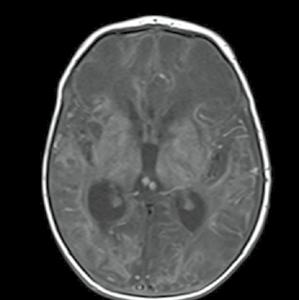

Novorozenec sedmý den po porodu, ženské pohlaví, extrémní nezralost, po porodu hypertonus, křeče.

Obr. A5.1–A5.4 Krvácení 3. stupně u novorozence (periventrikulárně, provalení do mozkových komor, krev zaplňuje více než 30 % objemu komor, hydrocefalus)